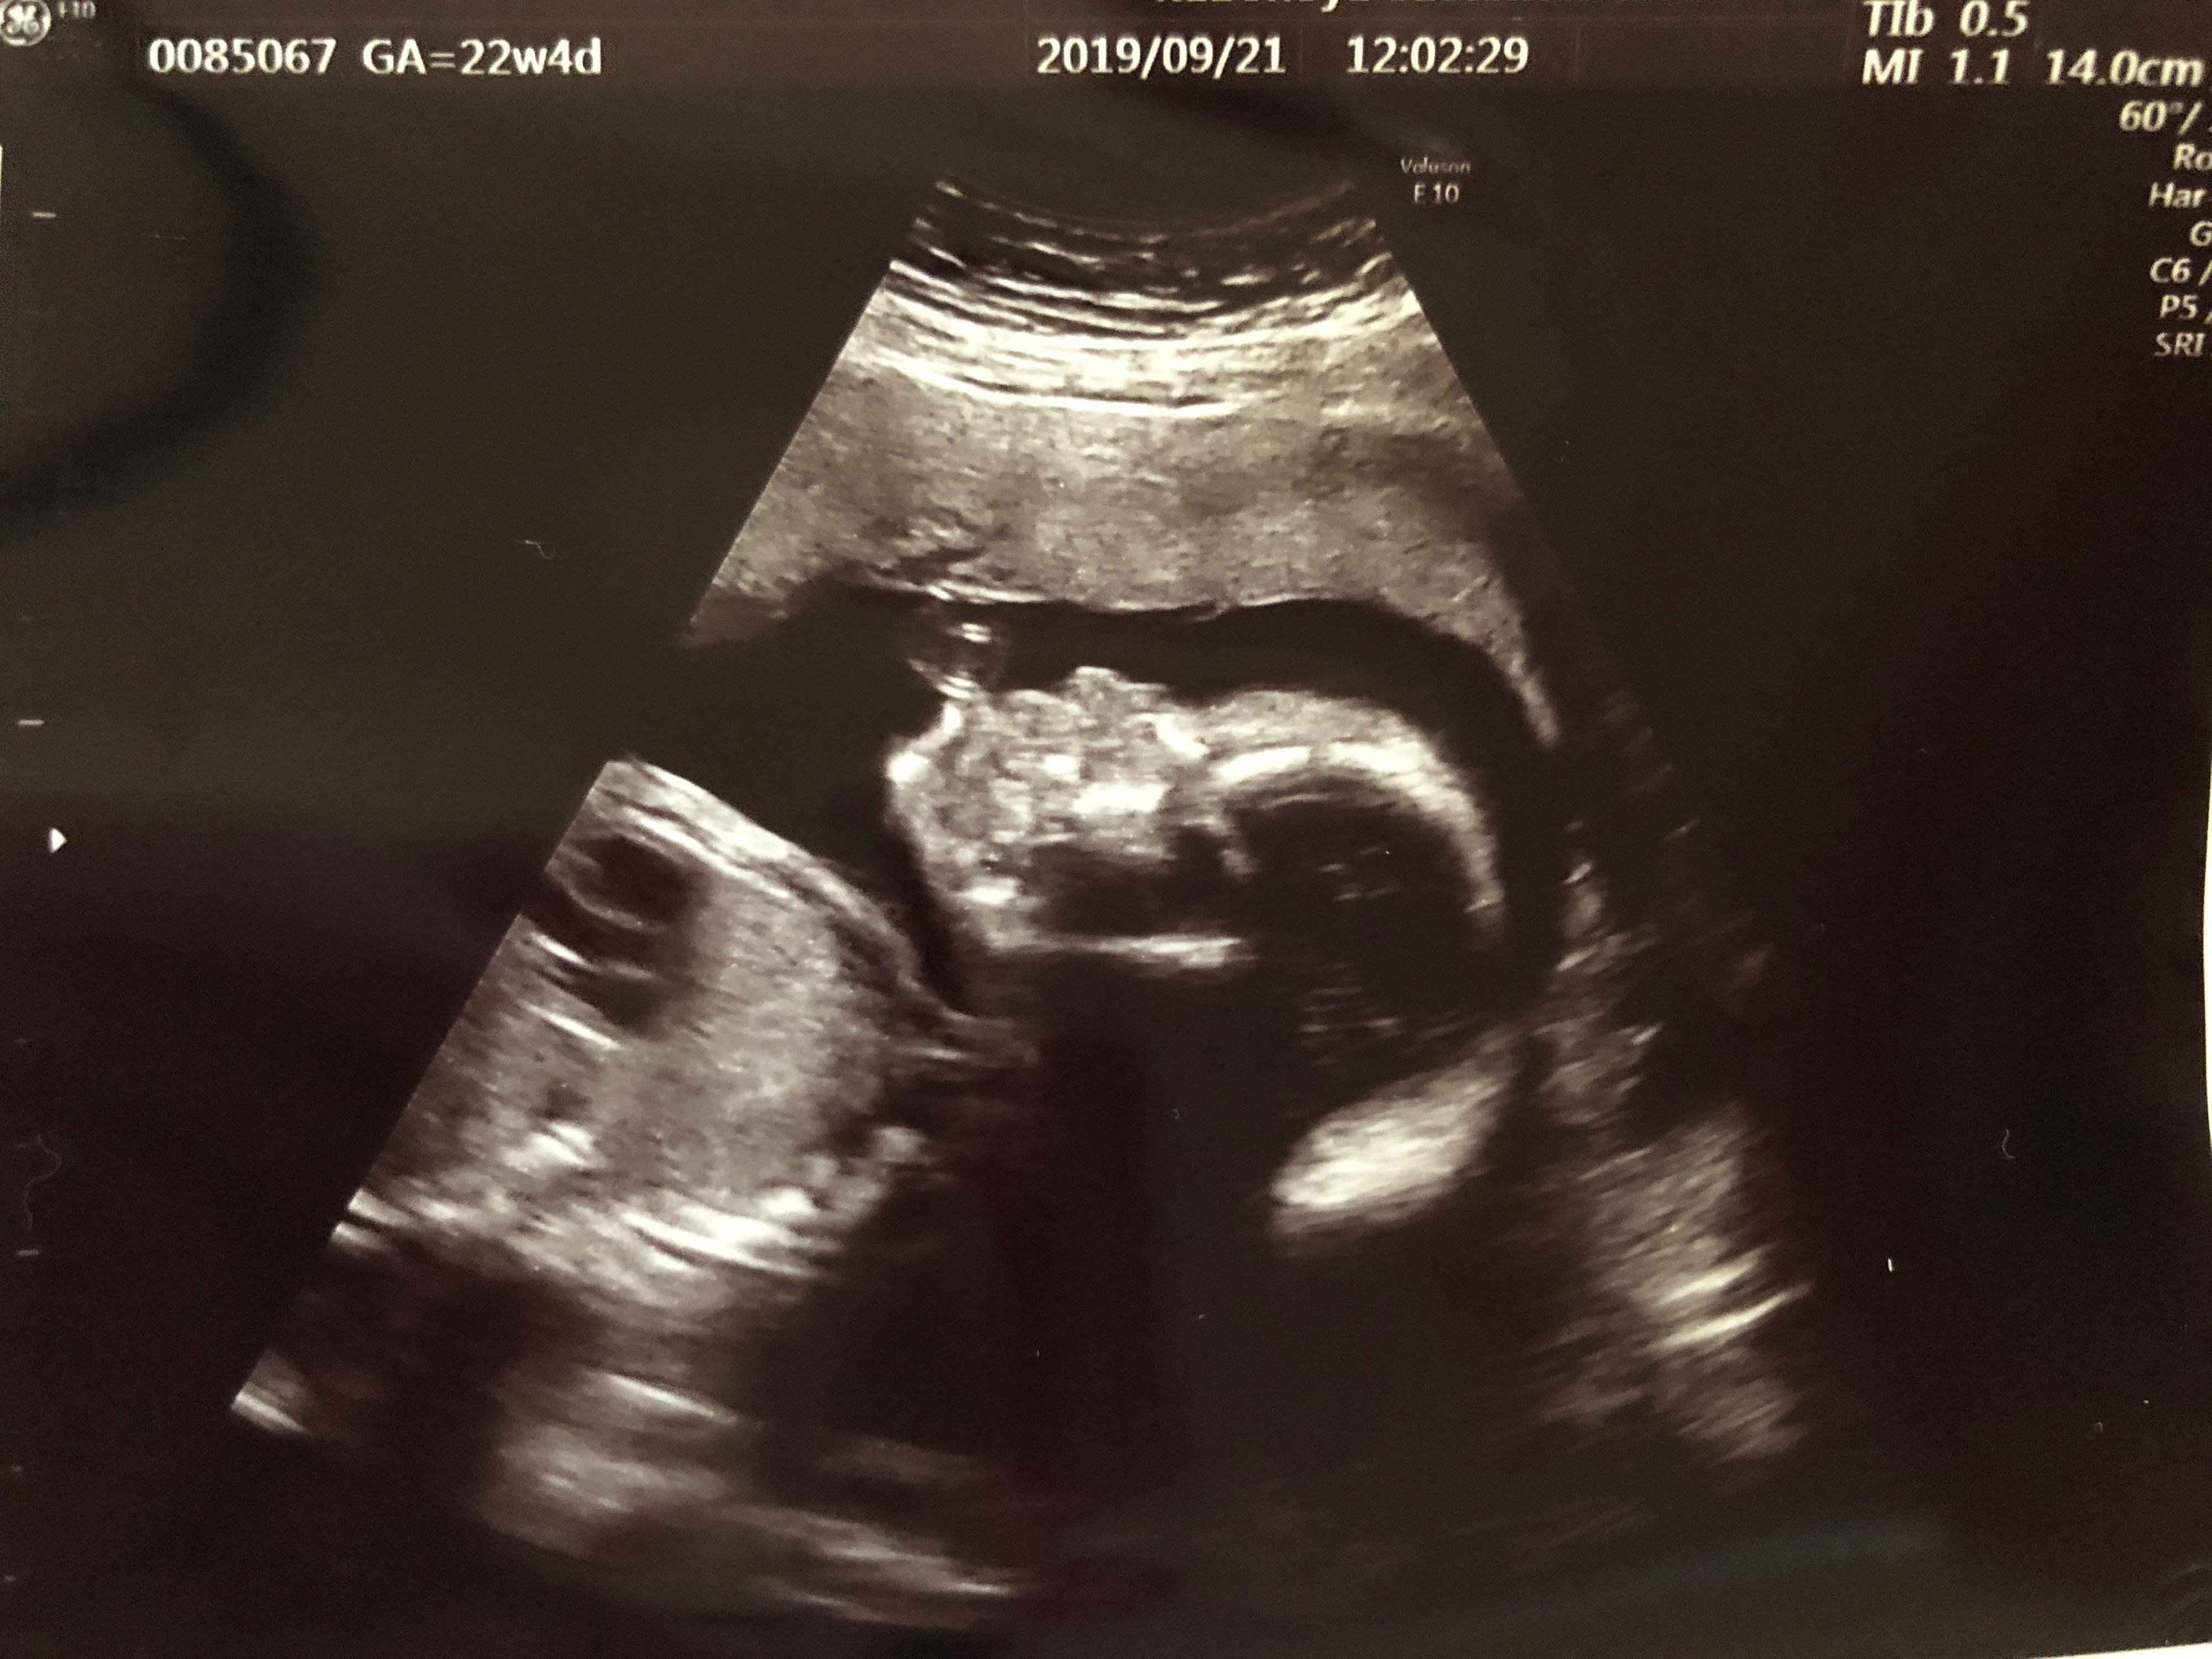

妊娠22週目 今度は体重増加!?

横顔を見ると、鼻や口、あごのラインがはっきりとわかるようになりました。この頃、つわりが落ち着いてきて、今度は食べることが楽しくなってしまい、健診のたびに体重が増えてしまいました。つわり中に大幅に減った分、問題にはなりませんでしたが、気をつけるようにと先生からも注意が…。